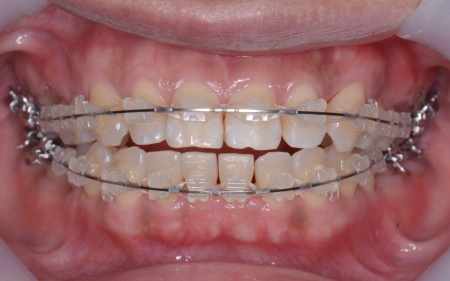

矯正方法としては、上下の歯全体の表面にブラケットと呼ばれるボタン状の装置を接着し、そこにワイヤーを通して歯を動かすマルチブラケット装置を採用しました。

とくに上の左右奥歯には、矯正用ミニインプラント(矯正治療専用の小さなネジ)を埋入し、奥歯を歯茎の方向に押し下げる「圧下」という治療を行っています。これにより開咬が解消され、前歯でしっかり噛めるようになりました。

マルチブラケット装置で矯正治療中です。